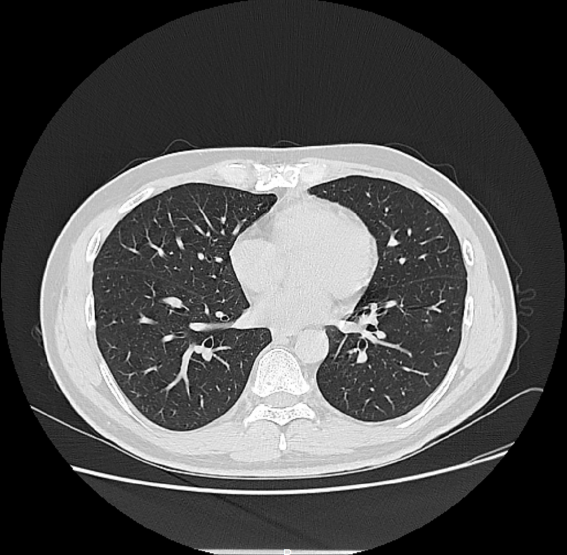

根据在胸部CT上的表现,又可将肺结节分为:纯磨玻璃结节、部分实性结节和实性结节。

大家第一次遇到肺结节,一般都是来自自己的胸部CT报告,报告上显示的可能是“增殖灶”,也可能是“磨玻璃影”,还可能是“实性小结节”等。

随着目前影像检查手段的进步,肺多发结节的发现也越来越多,一个患者可能两肺都有数颗小结节。